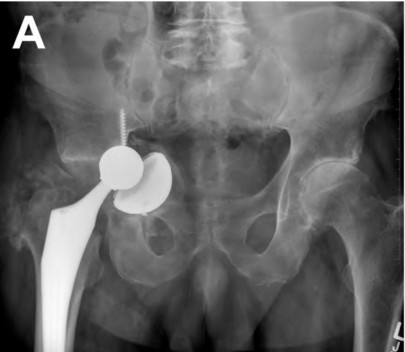

An 82-year-old woman falls and sustains the fracture shown in figure A. She denies any history of dislocation or prodromal pain prior to her fall. What is the most appropriate treatment?

The radiograph demonstrates a periprosthetic femur fracture extending to the tip of the stem. The long spiral fracture is consistent with a loose implant. The bone stock is sufficient. Therefore, this fracture pattern would classify as a B2 using the Vancouver classification system. The Vancouver classification for periprosthetic femoral fractures is simple yet incorporates all the pertinent factors such a location, stem fixation, and bone stock. Type A is a trochanteric fracture- lesser or greater. These can be treated non-operatively usually and ORIF if symptomatic. Type B fractures are around or just below the stem and are subdivided into three types. Type B1 is a fracture with a well fixed stem.

The treatment is cable plating or allograft struts or a combination of the two. Type B2 is a fracture with a loose stem with good bone stock. The treatment is a cementless porous coated long stem atleast two diameter length past the

fracture site. Type B3 is a fracture with a loose stem and comminution. For younger patients, use cementless porous coated long stems with allograft struts. For older patients, consider a tumor prosthesis. Cement fixation is sometimes necessary Type C is a fracture well below the stem tip. These can be treated independently of the prosthesis.

Figure A shows a lytic lesion of the proximal femur with an intramedullary implant. Figure B shows a proximal femoral replacement.